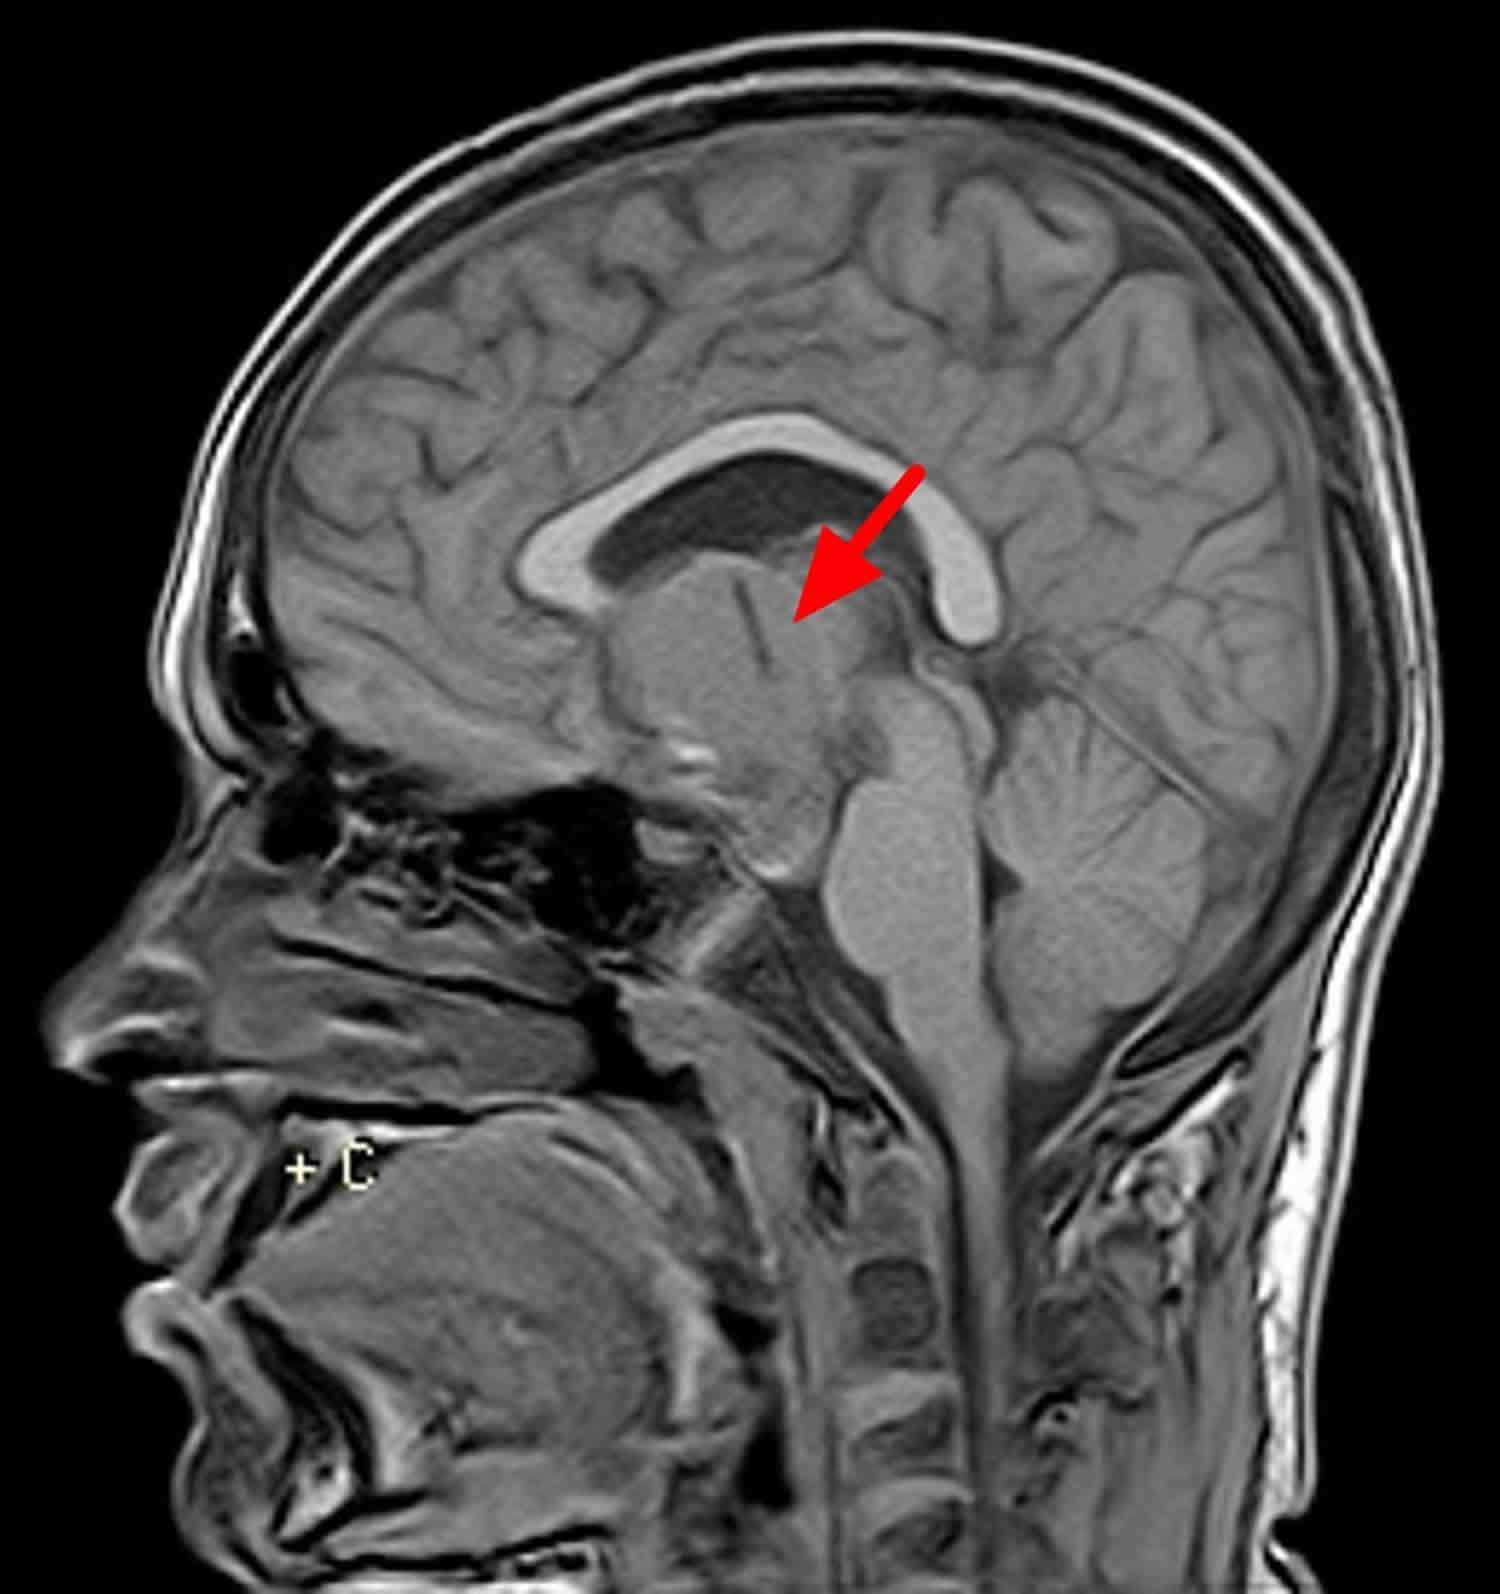

U sọ hầu là một loại u não không ung thư (lành tính) hiếm gặp.

U sọ hầu bắt đầu gần tuyến yên của não, nơi tiết ra các hormone kiểm soát nhiều chức năng của cơ thể. Khi u sọ hầu phát triển chậm, nó có thể ảnh hưởng đến chức năng của tuyến yên và các cấu trúc lân cận khác trong não.

- Xét nghiệm hình ảnh. Các xét nghiệm để tạo ra hình ảnh về não của bạn có thể bao gồm chụp X-quang, chụp cộng hưởng từ (MRI) và chụp cắt lớp vi tính (CT).